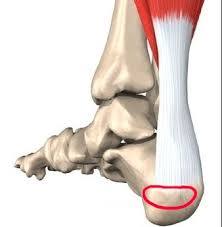

족저근막은 발바닥의 아치 모양 곡선을 유지하고 발에 전해지는 충격을 흡수하는 스펀지 같은 역할로 발바닥 근육을 감싸고 있는 얇은 막입니다. 이곳에 지속적인 충격, 마찰이 전달되면 결국 염증이 생겨 살살 걸어도 발이 아프게 됩니다.

물리적인 자극이 지속될수록 발뒤꿈치뿐 아니라 발 안쪽까지 아프고 쑤시는 증상을 보이기 때문에 가급적 빨리 치료할수록 경과도 좋은 편입니다.